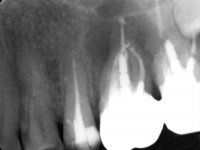

Male patient, 34 years old, non-smoker. Teeth 17 and 16 had extensive restorations with composite resin and placed intra-radicular posts. In the imaging examination, it was found that the endodontic treatment was not technically satisfactory, but had been asymptomatic for several years. The patient was rehabilitated with a 2-element bridge at 17 and 16 and 4 years later an abscess appeared in the apical area of 2.6. It had the 2.8 tooth included with a close relationship with the 2.7 root. During these 4 years there was no positional change of this tooth. After endodontic retreatment of teeth 27 and 26, an abscess appears again in the area of tooth 26, possibly associated with a root fracture. Given the history referred to in relation to tooth 26, it was considered a tooth with indicated extraction.

Teeth 17 and 16 were prepared for the fabrication of a 2-element Zr bridge. The impression was performed with a double mixing technique and a monolithic bridge in Zr was made in the laboratory. 4 years later, an abscess appeared in the apical area of tooth 26. It was decided to remove the bridge, remove the intra-radicular posts and retract the endodontic treatments of teeth 17 and 16. The removal of the bridge was carried out by making two cervical cavities. in the palatal area of the bridge and with a microluxator, disinsertion movements were performed. The intra-radicular posts were removed using fine drills and an ultrasound tip. The bridge was provisionally cemented and the patient was referred to a fellow endodontist for endodontic retreatment. After the retreatment, the intraradicular posts were placed again and the bridge was definitively cemented. One year later, a new abscess appears, possibly related to a root fracture. The bridge was sectioned between tooth 27 and 26 and tooth 26 was extracted and the crown of 27 was provisionally cemented. 3 months later, teeth 27 and 25 were prepared and a temporary bridge was made in dual polymerization resin. Then, an impression was made using the double mixing technique and a 3-element bridge in Zr was made in the laboratory. It was permanently cemented in the mouth with resin-reinforced glass ionomer cement.